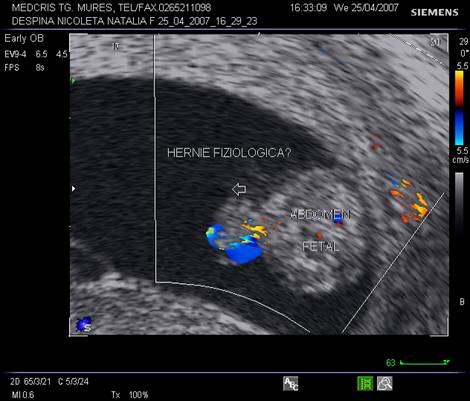

recunoasterea herniei fiziologice abdominale fetale ce apare la 9 - 10 sapt si dispare la 12 - 13 sapt

Fig. nr. 27. Hernie fiziologica la fatul de 11 sapt., sectiune transversala abdominala, la ecografia transvaginala